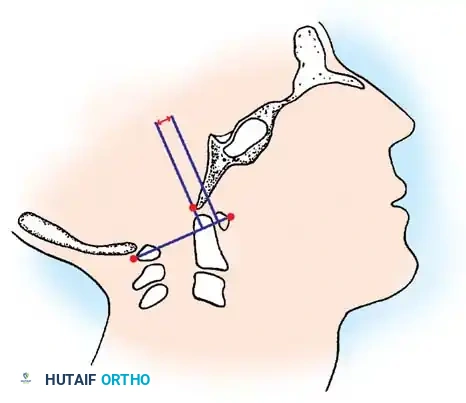

3. Powers Ratio

The Powers ratio is the most widely utilized metric for diagnosing anterior or posterior atlantooccipital translation. It is calculated by drawing two lines:

1. Line BC: From the Basion (B) to the posterior arch of the atlas (C).

2. Line OA: From the Opisthion (O) to the anterior arch of the atlas (A).

The length of line BC is divided by the length of line OA (BC/OA).

* Normal: ~0.77

* Anterior Translation: A ratio > 1.0 is diagnostic of abnormal anterior translation of the occiput.

* Posterior Translation: According to Parfenchuck et al., a ratio < 0.55 indicates abnormal posterior translation.

Fig. 37-36 Powers ratio. A ratio greater than 1 is diagnostic of anterior atlantooccipital translation, and a ratio less than 0.55 is diagnostic of posterior translation.